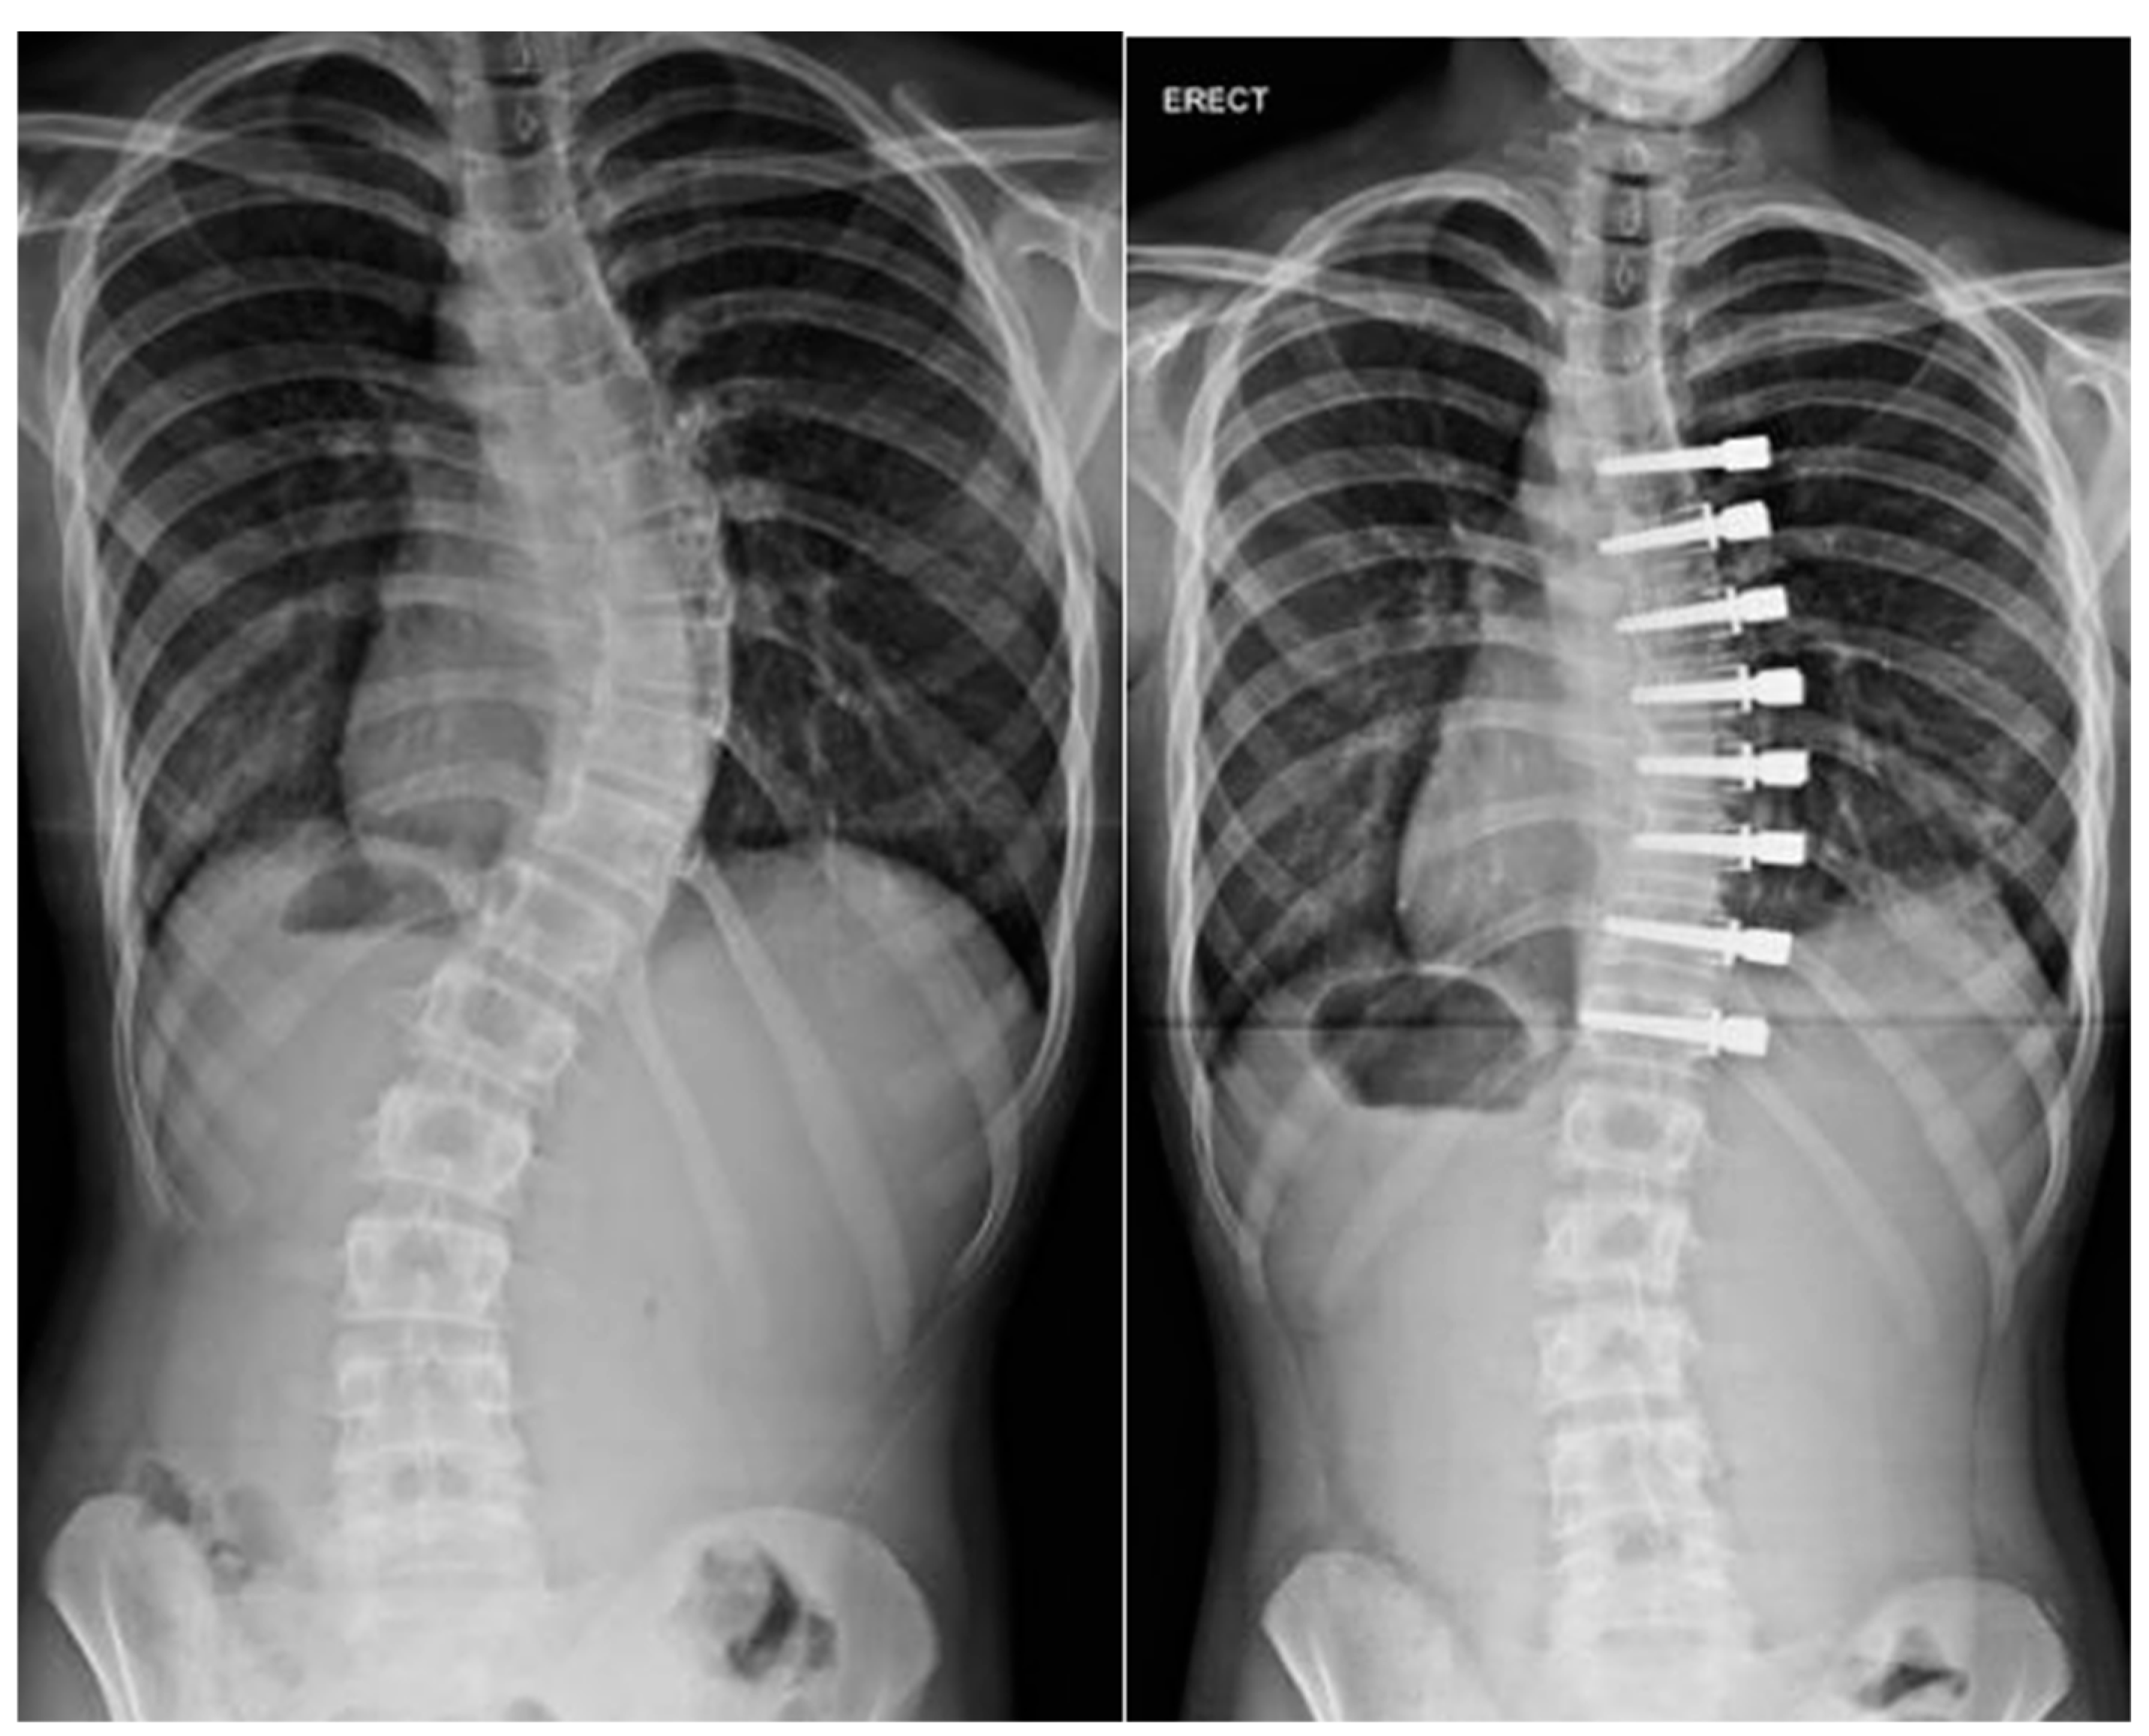

In an effort to address the drawbacks of distraction-based implants including the inability to mimic continuous physiological spinal growth [52], stiffness, and the “law of diminishing returns”, as well as implant failures and expense, the spring distraction system (SDS) was developed. The SDS consists of one or more compressed springs positioned around a standard sliding rod to provide active continuous distraction of the spine to stimulate growth and further correction. Early prospective data demonstrate an average 51% reduction of curve with this device as well as low adverse events or unplanned returns to the operating room at a rate of 0.1 per patient per year [53].

Child with Goldenhar syndrome and severe cervicothoracic kyphoscoliosis at preop, immediate postop, and 6 years postop with gradual correction with the spring distraction system in Figure 3 (images courtesy of Dr. RM Castelein).

Figure 3. Preop, immediate postop, and 6 years postop with gradual correction with the spring distraction system.